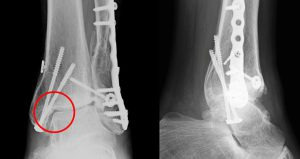

- 금속 판(플레이트)·나사(스크루)·강선(K-wire)로 정복·고정 후 2주 내 실밥 제거, 4~6주 고정 유지.

Tip: X-ray·CT로 정렬이 완벽히 맞아야 관절염 발생을 억제할 수 있습니다. “통증만 줄면 됐다”는 생각보다 정렬 정확도가 예후를 좌우하므로, 전문의 촬영 사진을 보고 설명을 꼭 들으세요.

Q3. 금속 나사는 언제 빼나요?

A. 관절면을 침범한 나사는 12~18개월 후 제거를 권고하지만, 불편·염증이 없으면 평생 유지하기도 합니다. 결정은 CT·통증 정도·생활양식에 따라 달라집니다.